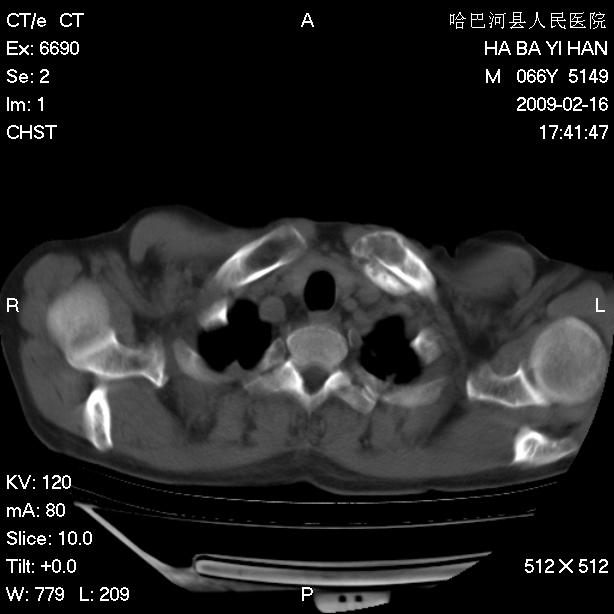

以下是引用huangxun4321在2009-2-16 20:18:00的发言:[br]部分病灶可见硬化边,部分可见骨质破坏消失,部分病灶内可见骨脊,说明病灶内既有良性病变,又有恶性病变,考虑骨巨细胞瘤恶变,未除骨纤恶变,畸形性骨炎少见,亦要考虑.

以下是引用731208在2009-2-16 20:31:00的发言:[br]考虑恶性胸膜间皮瘤并肋骨,脊柱转移。

以下是引用yijiansheng在2009-2-16 20:16:00的发言:[br]考虑恶性胸膜间皮瘤并肋骨,脊柱转移。

以下是引用形影不离在2009-2-16 19:55:00的发言:[br]考虑多发性转移瘤。